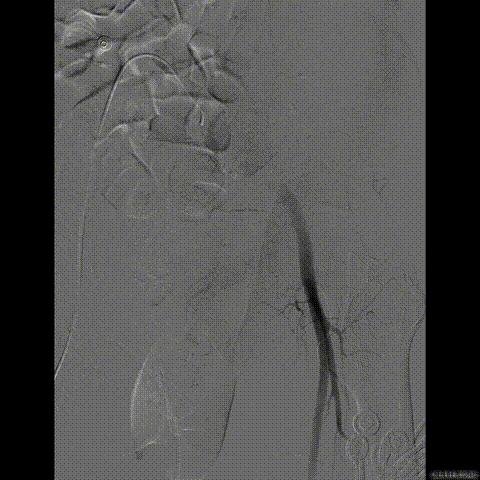

行急诊手术 腹主动脉及左侧股动脉造影

左侧股动脉见造影剂外渗

球囊压迫后植入覆膜支架

复查造影